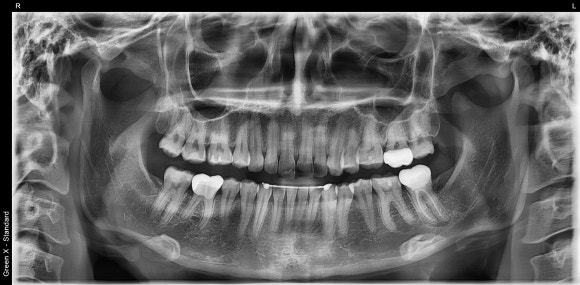

안녕하세요.

신촌치아지킴희 전준희 원장입니다.

저는 치과보존과 전문의입니다.

자연치아의 상태를 진단하고

그에 맞는 치료를 하는 것이 제 업입니다.

20대 여성 환자분께서

오른쪽 어금니의 참지못할 시린 증상을 안고 오셨습니다.

검사결과

오른쪽 아래의 크라운을 씌운 치아에서

극심한 통증이 발생하는 것을

알 수 있었습니다.

크라운의 상태는 나쁘지 않았습니다.

이전의 충치가 깊었다고 하셨습니다.